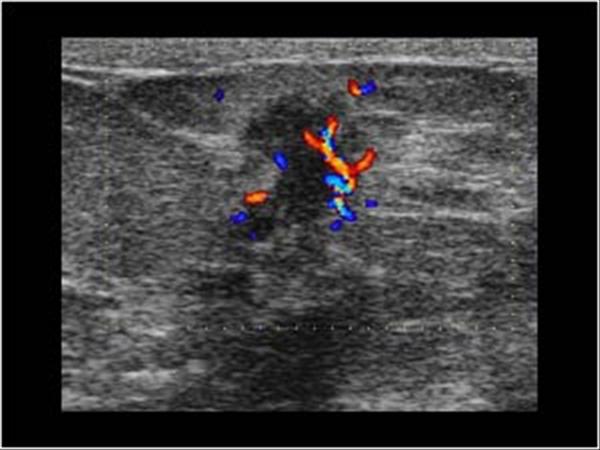

Ung thư vú

Ung thư vú - Ảnh 3

» Thông tin: Nữ giới – 59 tuổi.

» Lâm sàng: Khối tuyến vú.